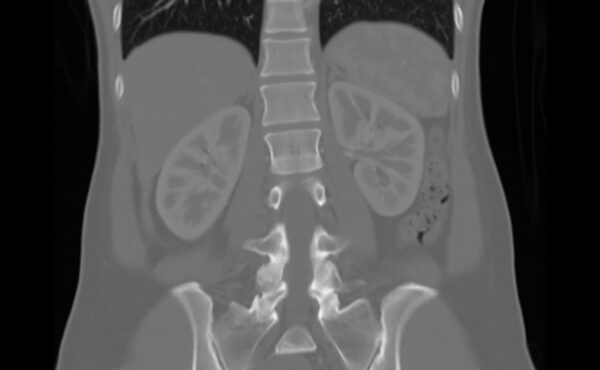

My kidneys, as seen in a 2018 CAT scan.Courtesy of Wency Leung

My decision to donate an organ was easy. Much harder was choosing which to give.